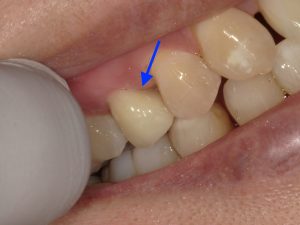

治療前

赤い矢印部分、黒くなっているところが虫歯です。虫歯が神経まで感染していたため、神経を取る処置「抜髄」を行いました。当院では根管治療を行う際には必ずマイクロスコープとラバーダムを使用します。マイクロスコープ・ラバーダムを使用した精密根管治療について詳しくはこちらをご覧ください。